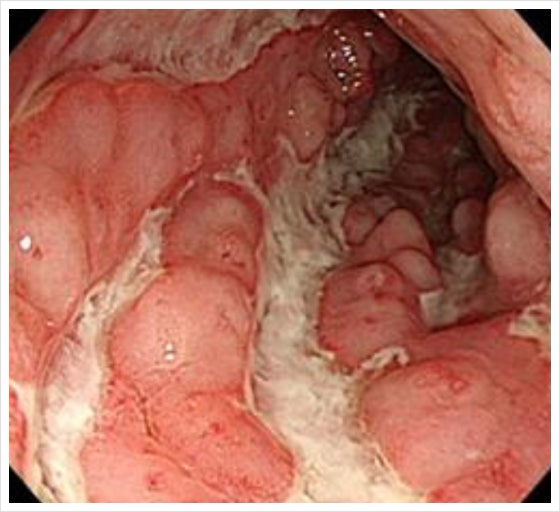

크론병, 궤양성 대장염으로 대표되는

염증성 장 질환은

현재 의학으로 완치가 어렵습니다.

염즘성 장질환 염증성 장질환 염증성 장질환은 장에 발생하는 원인 불명의 만성적인 염증을 뜻하며 통상적으로는 특발성 염증성장질환인 궤양성대장염과 크론병을 지칭하지만 우리나라에 비